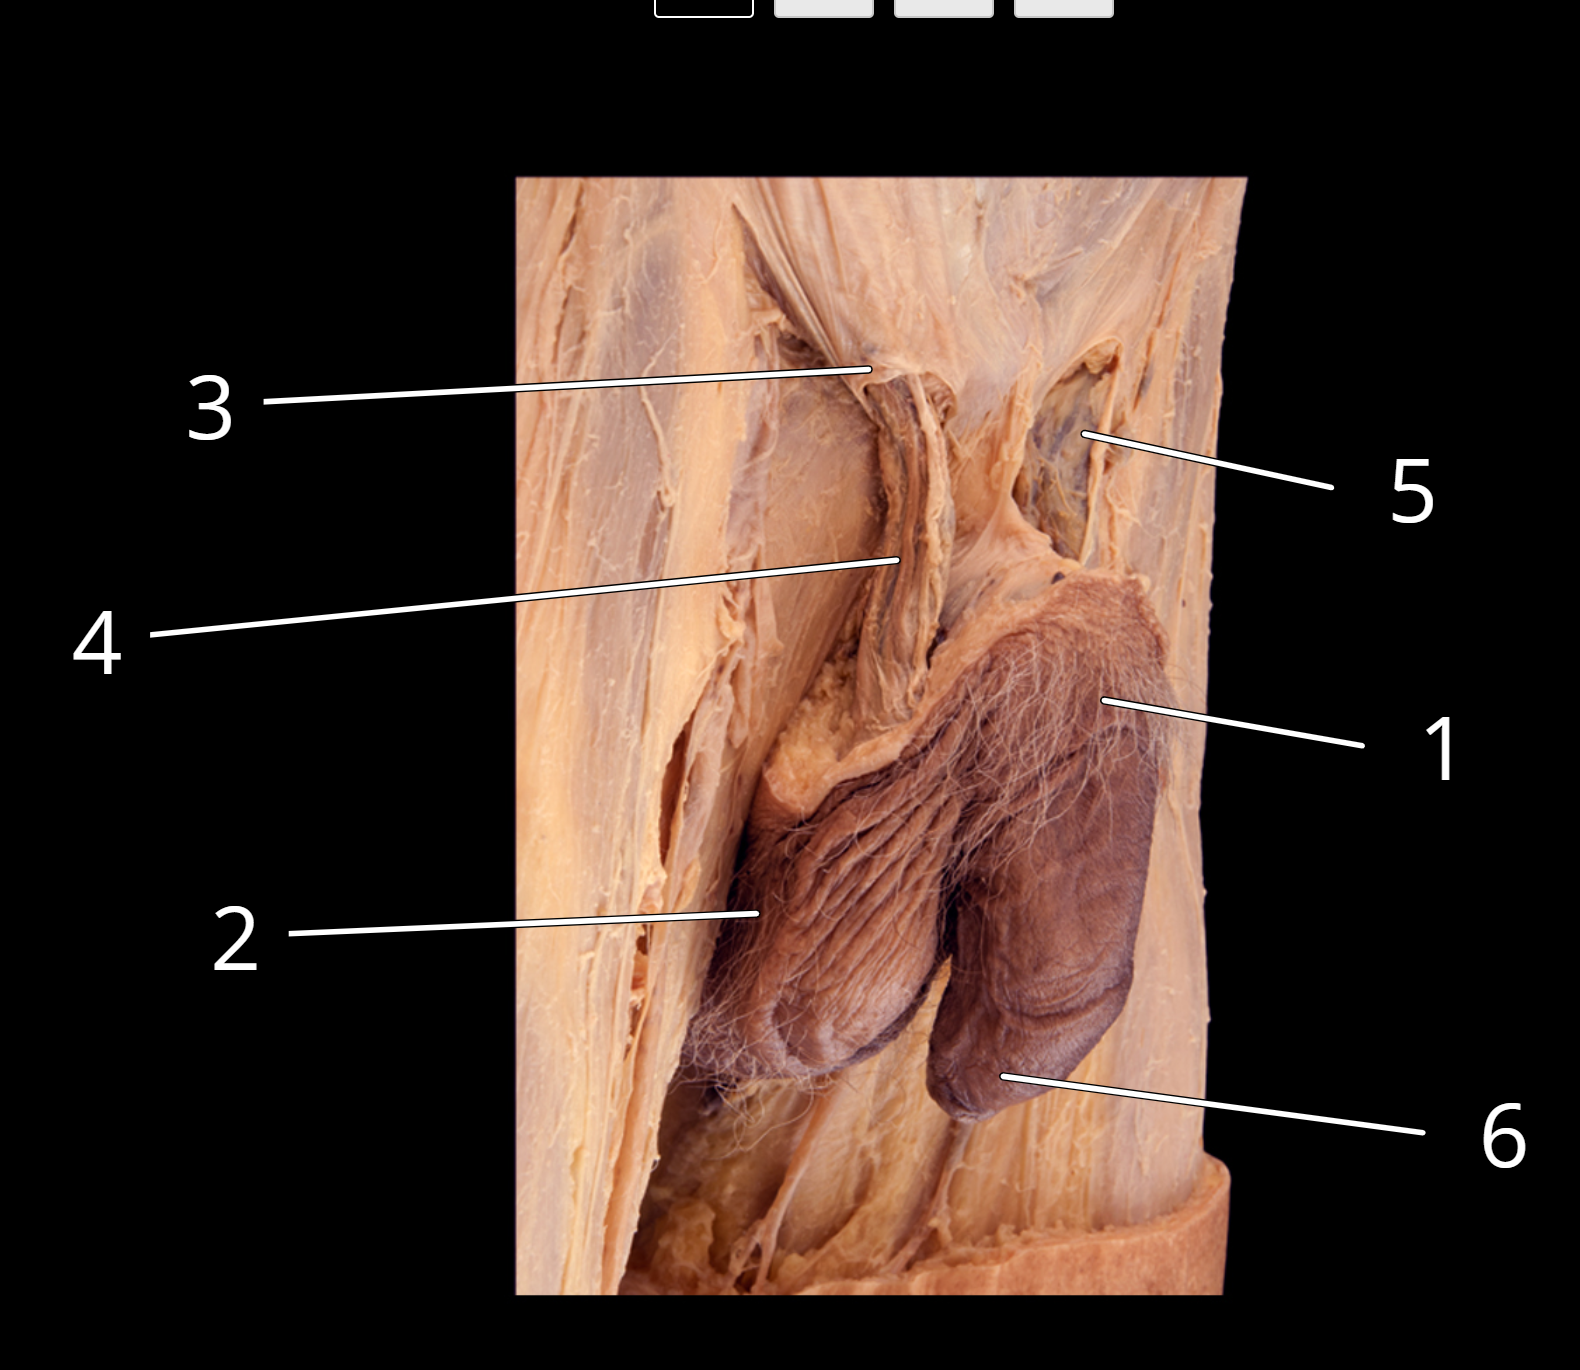

Penis and testis, lateral view

1. Penis

2. Scrotum

3. Superficial inguinal ring

4. Right spermatic cord

5. Left spermatic cord

6. Prepuce